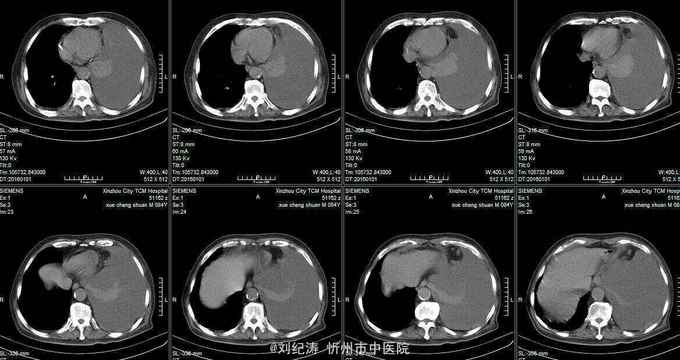

查体:ECOG评分:3分,生命指征平稳,浅表淋巴结未触及明显肿大,双眼睑无水肿,唇无发绀,颈软,双侧胸廓对称,左肺语颤增强,左肺呼吸音消失,右肺呼吸音粗,可闻及哮鸣音,心律齐,腹平软,肝脾肋下未触及,移动性浊音阴性,肠鸣音3次/分,双下肢无水肿。 辅助检查:血常规(2016.1.1):WBC:10.6*109/L,RBC:4.69*1012/L, PLT:165*109/L ,HGB:167g/L.生化(2016.1.1):谷丙转氨酶11U/L,谷草转氨酶11U/L,总蛋白60g/L,白蛋白33g/L,尿素:9.8mmol/L,肌酐:123umol/L,尿酸:251 umol/L,血糖:7.37 mmol/L;电解质:钾:4.79mmol/L,钠:123.5 mmol/L,氯:85.7 mmol/L,钙:2.03 mmol/L。肺部CT(2016.1.1):左肺完全萎缩,左侧胸腔大量积液,右肺未见异常,纵膈轻度右移,未见明显肿大淋巴结。

诊断: 1.左肺癌 左侧胸腔积液 左肺不张;2.2型糖尿病;3.低钠、低氯血症;4.低蛋白血症 治疗 完善检查,予以胸腔穿刺置管引流胸水以减轻心肺负荷,静脉给予抗感染、祛痰、止咳、平喘、提高免疫、扶正抑瘤、营养支持、调节电解质平衡及对症治疗。

现患者胸腔引流血性胸水2000ml,症状略有改善;为进一步控制胸水、控制肿瘤进展,拟行胸腔药物灌注,由于患者高龄,大家讨论下灌注什么药比较合适?另有无口服依托泊苷指征?